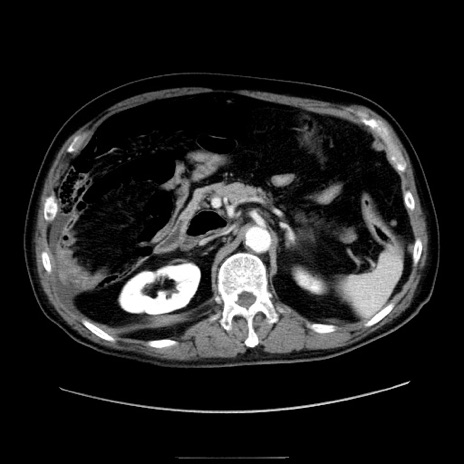

症例30(横断像)

【症例】80歳代男性

【主訴】臍周囲痛

【現病歴】約6時間前から臍下部痛が出現。次第に腹部膨隆・背部痛も生じてきたため来院。背部痛の場所は変化しない。

【身体所見】意識清明、BT 36.3℃、BP  131/87mmHg、P 87bpm、SpO2 100%(RA)、臍周囲自発痛・圧痛あり、反跳痛なし、自発痛部位に一致して板状硬あり、腹部膨隆、腸雑音減弱、CVA tenderness両側陰性。

【データ】WBC 19600、CRP 0.33